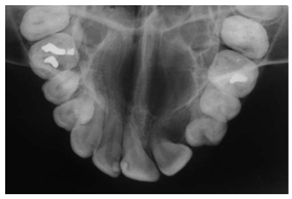

| Type | Publication Used | Variable Measured | Sample Image | Features |

|---|---|---|---|---|

| Bitewing X-rays | [37,49,54,77,84,85,86] | Caries detection (posterior initial proximal caries) | ![]() | Accuracy |

| Occlusal X-ray | N.A | Detecting abnormal, extra teeth, jaw fractures, a cleft palate, cysts and abscesses | ![]() | Displaying a section or entire arch of teeth in the upper or lower jaw |

| Periapical X-rays | [12,39,40,59,86,87,88,89,90,91,92,93] | Diagnosing invisible proximal dental caries | ![]() | Display the entire tooth, from the crown to the root, where it connects to the jaw. |

| Radiovisiography (RVG) | [36,42] | Diagnosis of an individual tooth and classification of dental diseases. | ![]() | No films placed inside the patient mouth. |